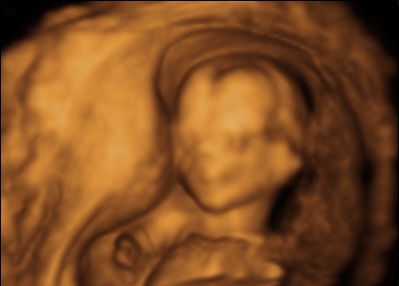

私も妊娠初期から妊娠中期にかけて、2Dと4Dの超音波検査を行った。

2Dとは平面画像、4Dは立体画像にさらに時間を加えたもので、お腹の中で動いている赤ちゃんの様子をリアルタイムで見られます。

4ヶ月(12週2日) 4ヶ月(12週2日)

どアップで撮ってもらったおかげで、 のびのびと両腕をストレッチ。

頭・手・足・胴がよくわかり、耳の位置までハッキリと。 おめめが覚めたのかな?

ひざをちょこんと曲げ、両手はグーでおなかの上に。 手足を活発に動かせる様になって感激!

ラッコちゃん状態。嬉しさのあまり パパは映像画面に向かって「早く大きくなっ

ママの目はちょっとウルウル・・・

て」と話しかけていたね。